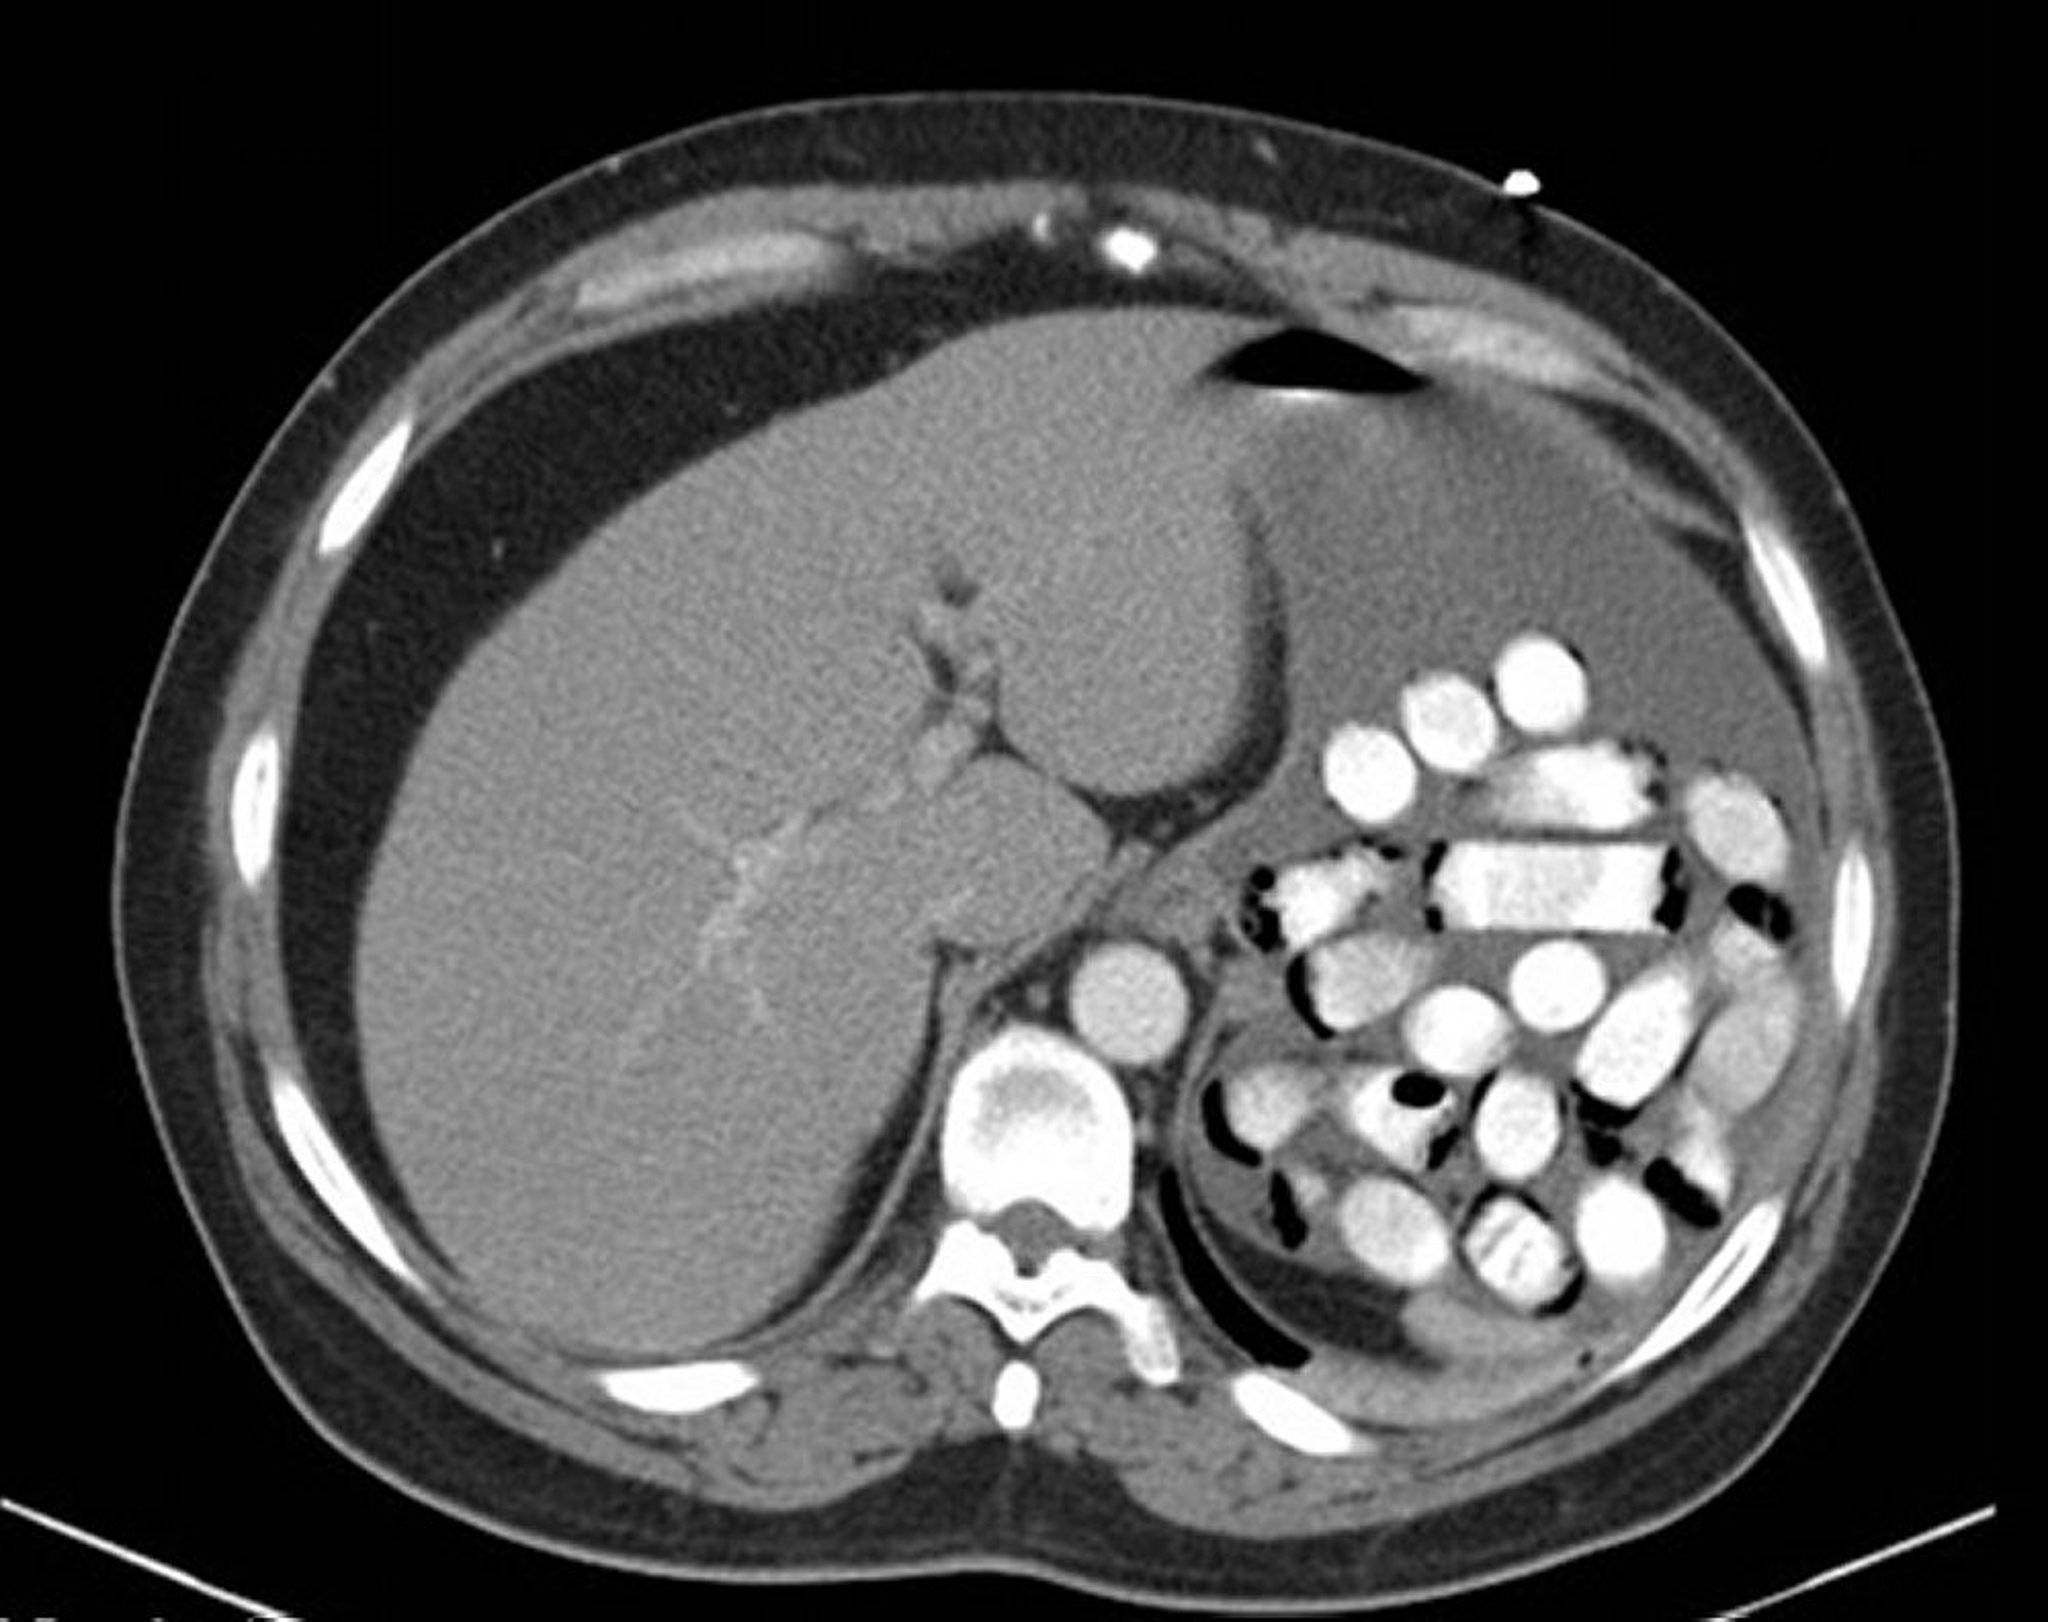

Corpo estranho gástrico (TC)

Essa imagem mostra pacotes de drogas no estômago.

Imagem fornecida por Alan Gingold, DO.